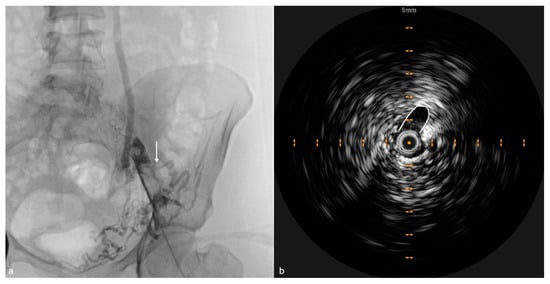

3. IVUS in Acute Lower Extremity DVT